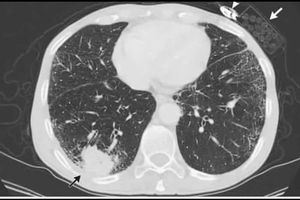

What is your diagnosis??

Lung cancer due to smoking

Fibrosis

iam student:D/D aspirational pneumonia as it at posterior portion of right lungs. further serology req